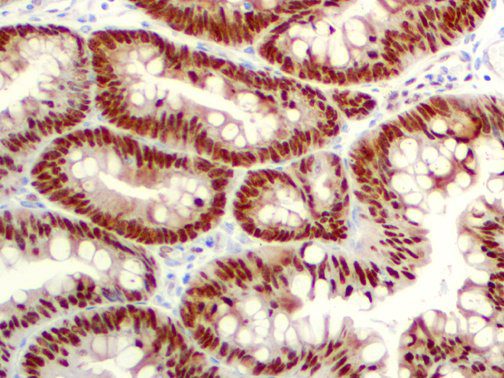

The first cytokines released are interleukin 1β (IL-1β) and tumor necrosis factor-α (TNF-α), which attract a variety of circulating white blood cells (WBCs) to the infection site, including neutrophils, monocytes, macrophages, and natural killer (NK) cells. This response, along with the antipathogenic chemicals released by these cells (i.e., complement), comprise the innate immune response. These cells directly attack the invading pathogen and also release additional cytokines, chief among them interleukin-1 and 6 (IL-6). IL-6 is essential for invoking the adaptive immune response, which calls T-cells, B-cells, and T helper (Th) cells to the infection site. IL-6 also stimulates further recruitment, proliferation and activation of macrophages.

This activation induces inflammatory monocytes to highly express IL-6, starting a localized and then systemic cascade effect that results in hyperproduction of IL-6, which accelerates the inflammatory process. Because IL-6 also increases vascular permeability, excessive levels cause blood vessels to become very leaky. This, along with clotting factors released from vascular endothelial cells, stimulates the coagulation cascade, resulting in microthrombosis (tiny clots), which leads to ischemia and tissue death of the kidney, intestines, heart, liver, brain and extremities.